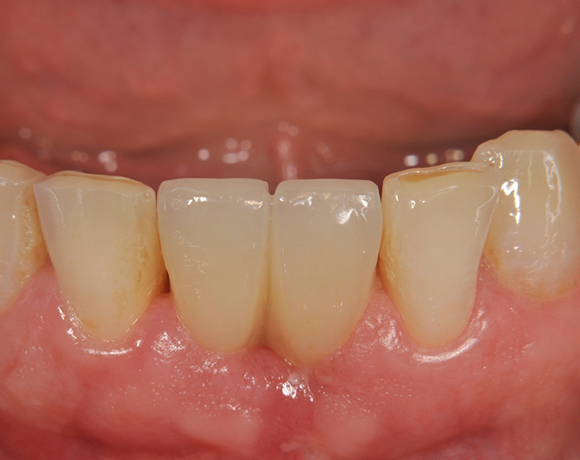

Zwei Unterkieferfrontzahn – implantate

Im vorliegenden Patientenfall wurden die beiden nicht erhaltungswürdigen, mittleren Unterkieferschneidezähne durch zwei Vollkeramikimlpantate ersetzt.